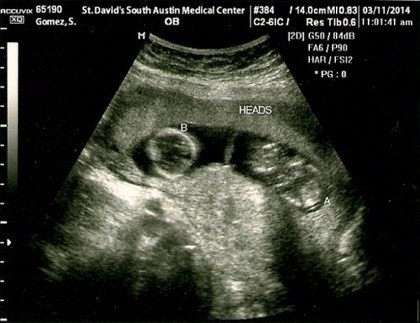

Kini beredar isu di internet kalau Selena Gomez hamil anak Justin Bieber. Isu ini sedang hangat diperbincangkan setelah muncul gambar hasil USG yang diduga milik pemain 'Arthur 3: The War of the Two Worlds' itu. Benarkah sonogram ini milik Selena?

Dalam sonogram tersebut terdapat nama pemiliknya yaitu Gomez, S. Hasil pemeriksaan menunjukkan bahwa ia hamil anak kembar. Terdapat juga nama rumah sakitnya di St. David's South Austin Medical Center serta waktu pemeriksaan pada Selasa (11/3/2014).

Sonogram itu kemudian beredar luas di internet yang membuat banyak orang bertanya-tanya apa benar hasil USG punya Selena? Saat dikonfirmasi ke pihak Selena maupun Bieber, keduanya menolak untuk diwawancara. Pihak mereka tidak ingin langsung menanggapi kasus ini.

Seperti yang dikutip dari Hollywood Life, setelah ditelaah kembali melalui detail lokasi dan waktu sonogram itu diambil sepertinya bukan milik Selena. USG dilakukan pada Selasa siang (11/3/2014) di St. David's South Austin Medical Center, Austin, Texas. Sedangkan bintang Disney itu sedang menjalani photo shoot untuk kampanye Adidas mendatang di New York, Amerika Serikat.

Beberapa pihak menduga USG dilakukan ketika Selena dan Bieber sedang di Austin untuk mengisi acara di SXSW. Namun kala itu Bieber tampil pada Senin malam (10/3/2014). Dari fakta yang ada terungkap bahwa hari dan lokasi pengambilan sonogram itu tidak sama dengan keberadaan Selena yang sedang di New York.

Selain itu ditemukan bukti lain yang menunjukkan kalau sonogram bukanlah milik Selena. Terdapat hasil USG yang identik dengan gambar tersebut di sebuah blog pribadi oleh wanita bernama Elle pada tahun 2009.

Untuk memastikan apakah memang ada sonogram yang sangat mirip seperti hasil USG yang diduga punya Selena dan Elle, dokter kandungan dari New York menegaskan bahwa itu tidak mungkin. Jadi kemungkinan besar sonogram telah diedit nama dan lokasinya.

"Semua sonogram dilihat berdasarkan perkembangan janin. Jadi itu sangat tidak mungkin ada dua sonogram yang identik satu sama lain seperti ini," tandasnya.